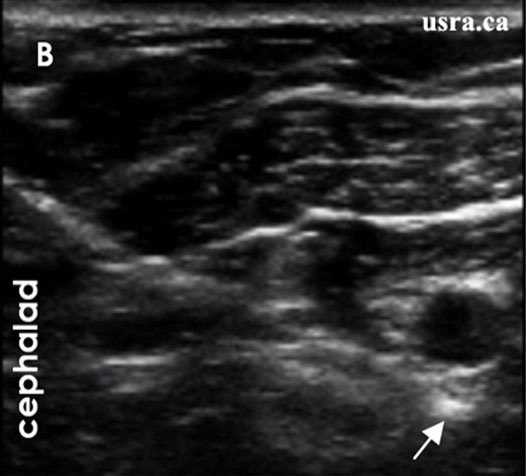

If an US-guided technique is used, with an in an in plane approach, the needle is inserted and advanced to reach the posterior aspect of the axillary artery (indicated by the arrow in Figures 9 and 10). Injection of a small amount of local anesthetic or D5W may be used to distend the perineural space and facilitate threading of the catheter. The catheter, simulating or non stimulating, would be advanced 3-5 cm perineural Afterwards, local anesthetic is injected through the catheter and spread of injectate observed under real time US guidance. The catheter may be tunneled if needed, and secured at the skin using steri strips and Tegaderm.

Figure 9. In plane approach with stimulating Tuohy needle for continuous perineural catheter placement.

Figure 10. Sonogram showing needle tip posterior to the axillary artery.

From usra.ca website, with permission.